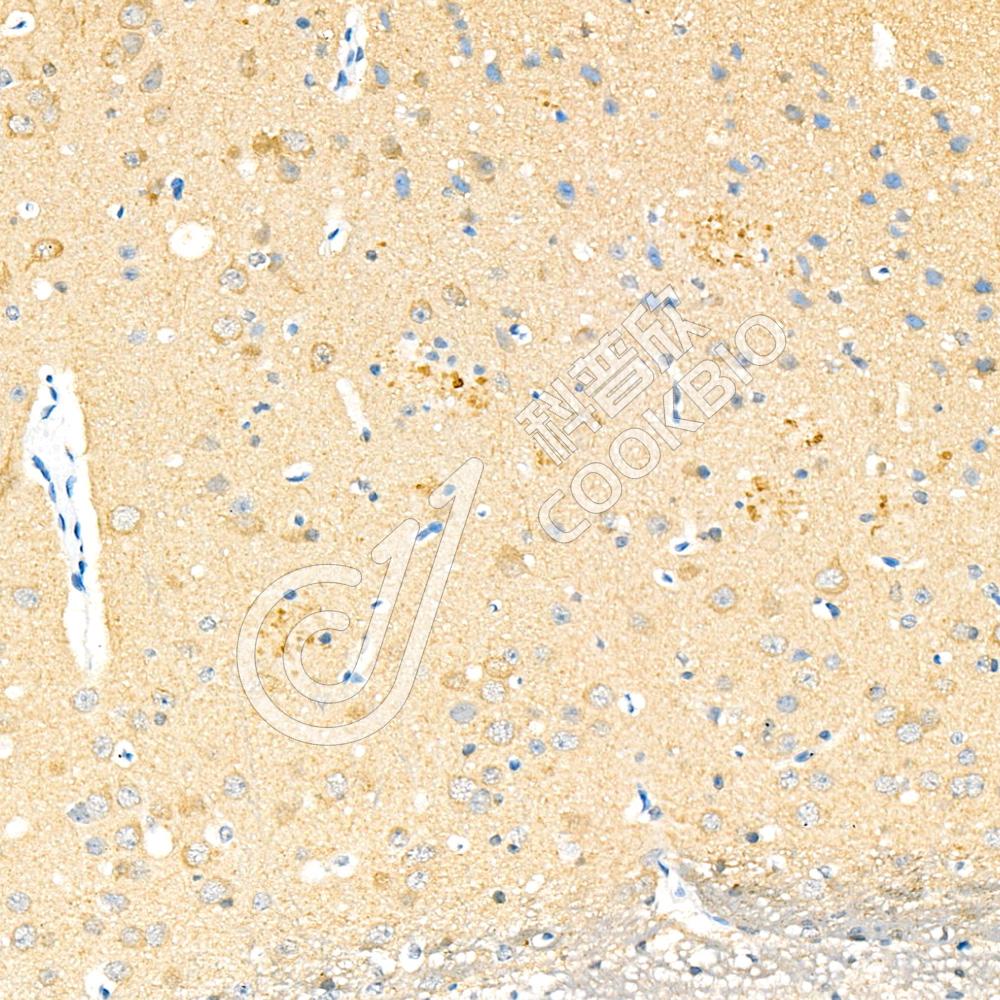

Anti-Phospho-TAU (S202/T205) 兔多克隆抗体

兔多抗

神经退行性疾病,修饰抗体

H,M,R

IHC/IF

|

Recombinant Anti-Phospho-Tau(S202/T205) antibody (兔单克隆抗体)

兔单抗

重组

神经退行性疾病,重组抗体,修饰抗体